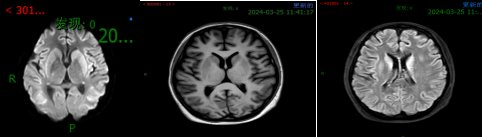

颅脑MRI:多发皮层信号异常

脑复苏后监测: